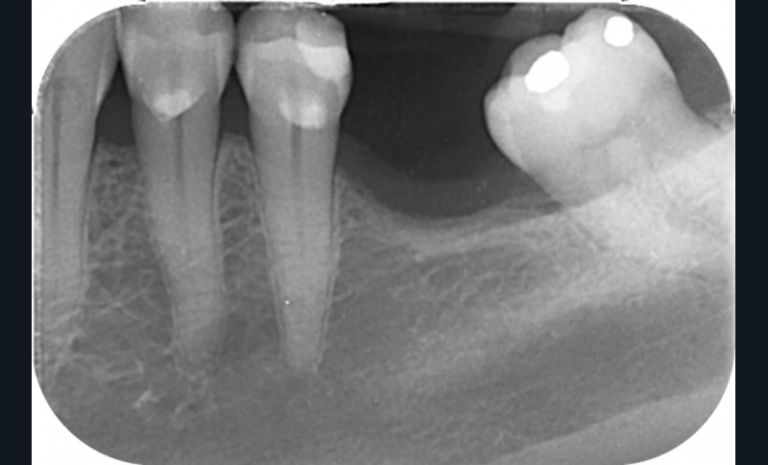

La perte d’une ou plusieurs dents entraîne la perte des points de contact, responsables de la stabilité et de la continuité de l’arcade. Par conséquent, une avulsion a pour première conséquence la migration ou la version d’une ou plusieurs dents distales (fig. 1 et 2). Cela est vrai en antérieur comme en postérieur.

L’âge de survenue de l’extraction semble avoir une importance sur l’apparition des migrations et des versions : si l’édentement intervient après 26 ans, les conséquences sont moins fréquentes [9].

Cette version, quand elle se produit, modifie les espaces interdentaires et complique l’hygiène proximale des patients. Des caries peuvent alors se développer en interproximal sans que cela soit forcément visible à l’examen visuel (fig. 3 et 4). Les radios de type bite-wing (rétro-coronaires) prennent alors tout leur sens (fig. 5 et 6).